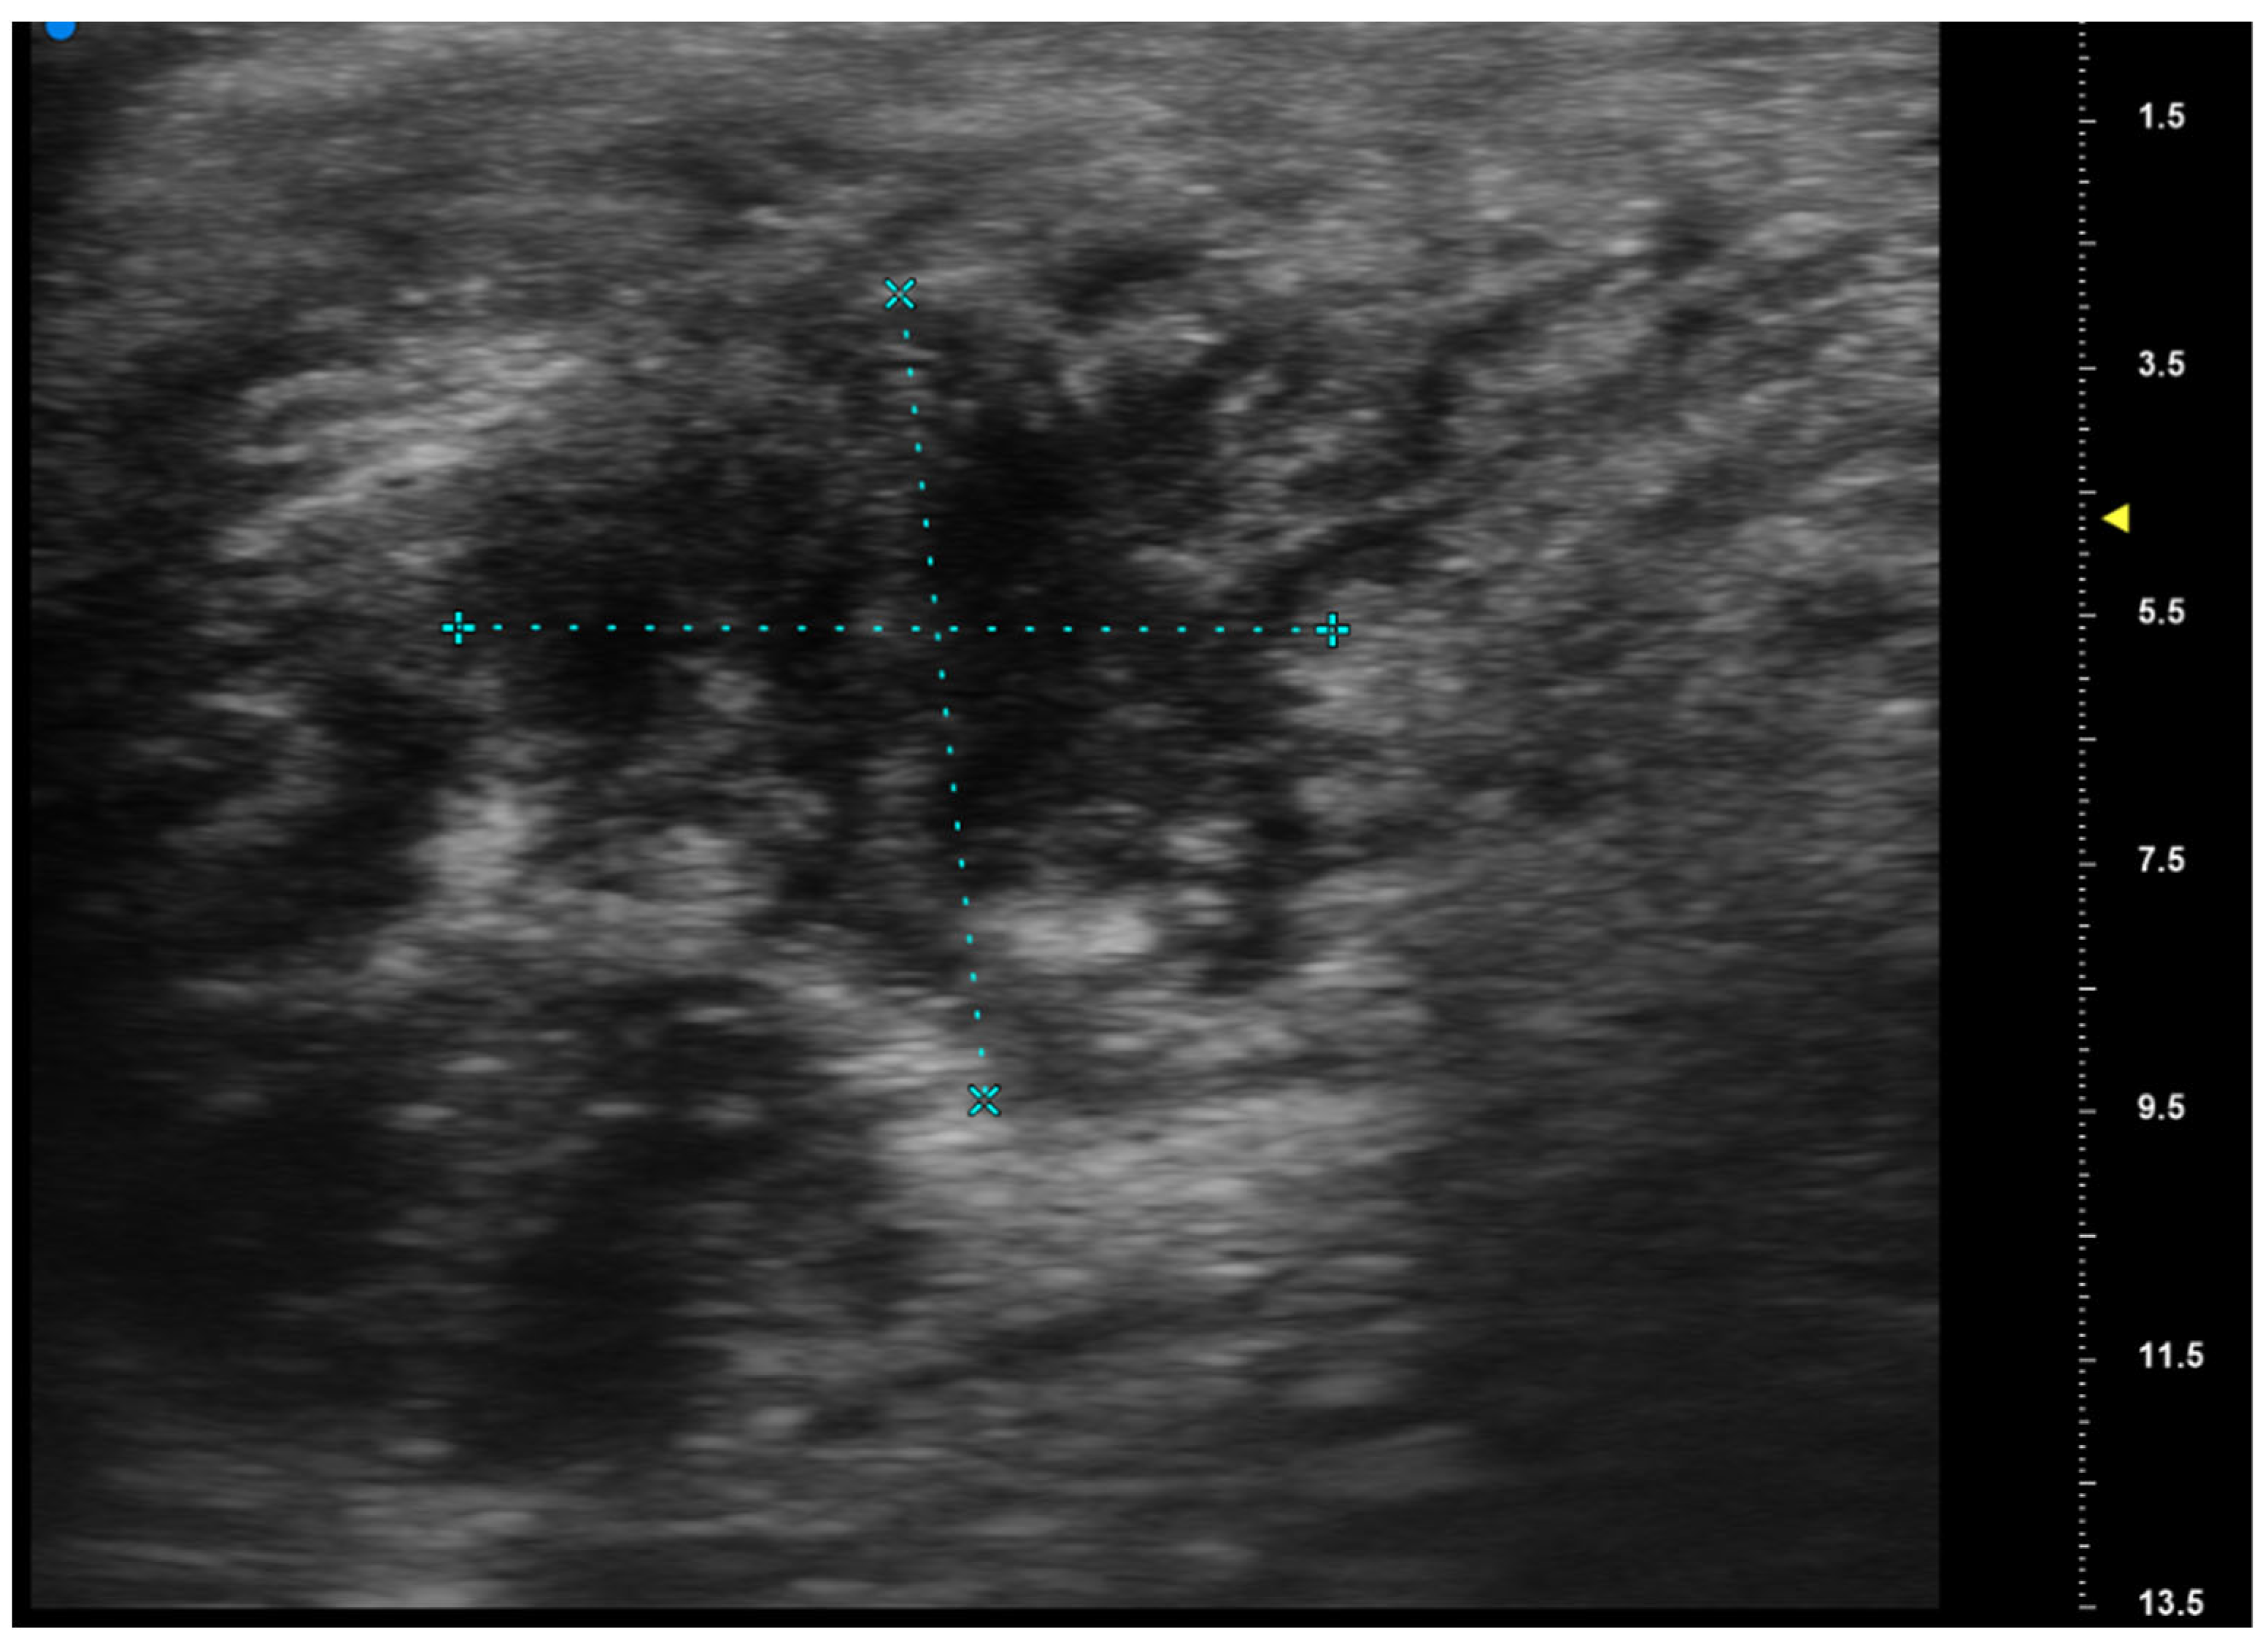

2.2. UHFUS Scan Protocol